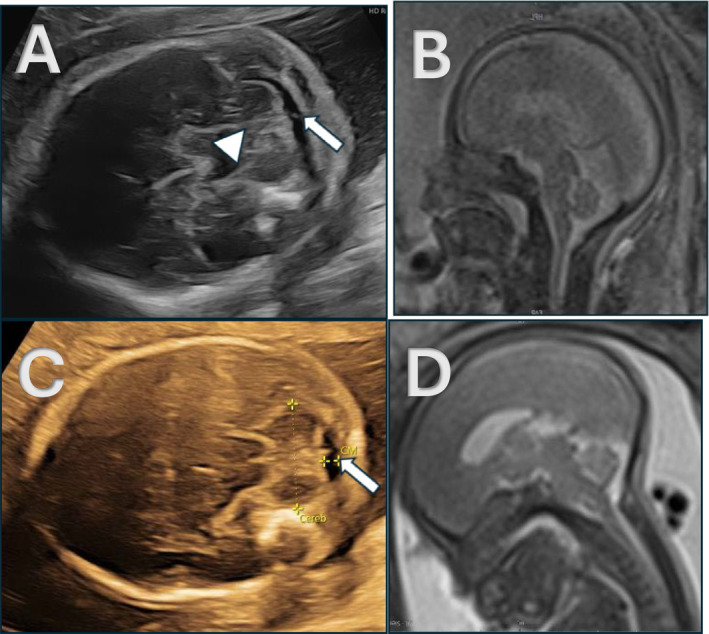

Objective: To report the natural history of fetuses with open spinal dysraphism (OSD) without hindbrain herniation (HBH) during second-trimester evaluation.

Methods: A multicenter retrospective cohort study was conducted across three prenatal centers to evaluate fetuses with OSD. We reviewed cases with postnatally confirmed OSD without prenatal HBH at 19-27 weeks. Standardized prenatal evaluation consisted of repetitive ultrasound and magnetic resonance imaging. Postnatal outcome measures involved imaging, intraoperative findings and neurological function tests.

Results: Among 280 fetuses with OSD, evaluated at a median gestational age of 21 weeks, a total of 12 (4%) lacked HBH. Moderate ventriculomegaly was observed in 33% of cases without HBH. Corpus callosum anomalies were not detected. Postnatally, HBH was present in 50%, while the shunt rate remained low (20%). In 80%, postnatal motor function (MF) was equal to or better based on the anatomical level. In 33%, MF after birth declined in comparison to the first fetal functional assessment in the second trimester.

Conclusion: Fetuses with OSD and absent HBH in the second trimester demonstrate a low postnatal shunt rate. MF was frequently impaired at the initial second-trimester assessment, and in about a third of cases, postnatal MF seemed to have worsened. These findings may inform counseling and question the place of fetal surgery for this subgroup.